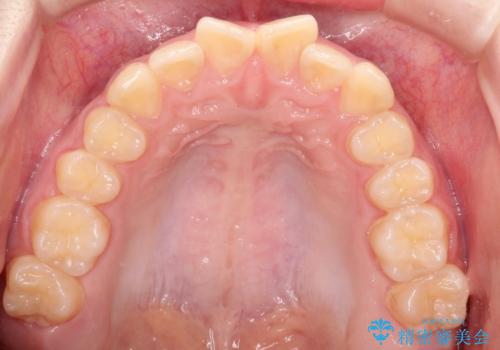

なるべく通院回数を減らして矯正したい インビザラインでのガタガタ矯正

- 上下の歯並びを治したいとのことで来院されました。

受験生ということもあり、なるべく通院回数を減らしての矯正を希望されたので、インビザラインで治療をすることにしました。